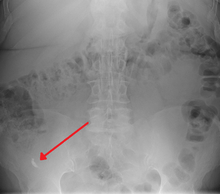

X-ray

In general, plain abdominal radiography (PAR) is not useful in making the diagnosis of appendicitis and should not be routinely obtained from a person being evaluated for appendicitis.[52][53] Plain abdominal films may be useful for the detection of ureteral calculi, small bowel obstruction, or perforated ulcer, but these conditions are rarely confused with appendicitis.[54] An opaque fecalith can be identified in the right lower quadrant in fewer than 5% of people being evaluated for appendicitis.[39] A barium enema has proven to be a poor diagnostic tool for appendicitis. While failure of the appendix to fill during a barium enema has been associated with appendicitis, up to 20% of normal appendices do not fill.[54]